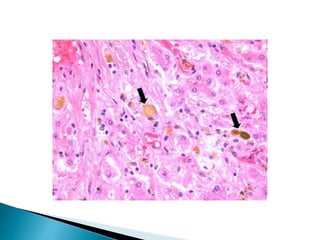

 Under a microscope, the individual hepatocytes will have a

brownish-green stippled appearance within the cytoplasm,

representing bile that cannot get out of the cell.

 Canalicular bile plugs between individual hepatocytes or

within bile ducts may also be seen, representing bile that

has been excreted from the hepatocytes but cannot go any

further due to the obstruction.

 When these plugs occur within the bile duct, sufficient

pressure (caused by bile accumulation) can cause them to

rupture, spilling bile into the surrounding liver tissue,

causing hepatic necrosis. These areas are known as bile

lakes, and are typically seen with extra-hepatic

obstruction.

HISTOPATHOLOGY